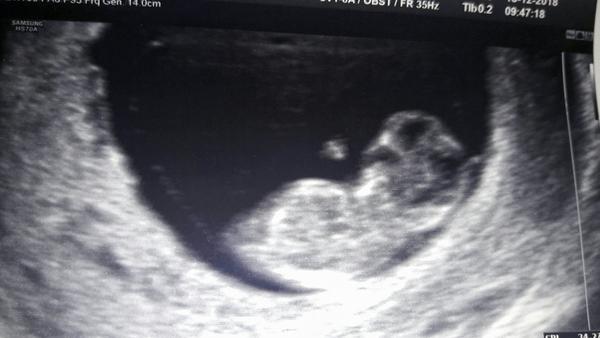

@juliia 💖🎉💖🎉krásná fotka. Moc gratuluji